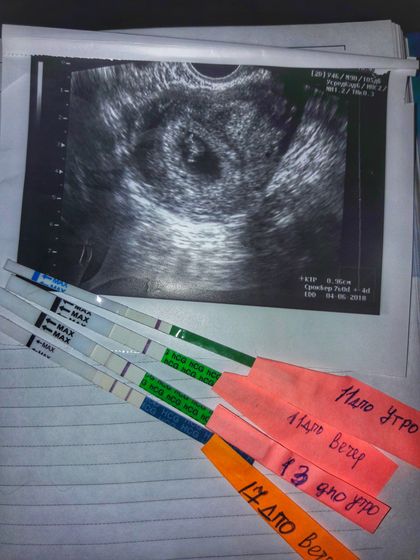

вот что нашла? решила написать историю?так быстро пролетело время? мы не планировали ребенка. Просто перестали предохраняться, были мысли «бог даст». В первый месяц ничего не произошло? а во втором месяце малыш выбрал нас? в общем просыпаюсь утром и иду делать тест, т.к у меня была задержка 1 день?(первый тест) сходила в туалет, сделала дела, посмотрела на тест вроде ничего, положила его в упаковку и в мусорку?сижу пью чай и вдруг, меня что-то дернуло достать его и еще раз посмотреть⚠️муж спит?когда я его дастала, не верила глазам?бужу мужа с вопросом: ты глазастый? На что он ответил: ну да? показываю, рассматривали вместе, муж говорил: не вижу? в течении дня, меня не покидала мысль, что я видела // полоски. Покупаю тест, делаю дела вечером(второй тест) и уже видно? но сомнения были, ведь тесты у нас бывают с браком? решили подождем. Месячных нет. И вот (третий тест утро) я не верю своим глазам, бегу на кухню, сидит муж пьет чай ни о чем не думая?я не смогла сдержать слёзы?показываю тест?у мужа на лице улыбка и слезы?этот момент не передать словами?мы плакали вместе обнимая друг друга и пытались (от шока) что-то объяснить нашему коту??? муж уезжает в рейс(дальнобойщик) я иду вставать на учет в 7 недель, отправляют на первое узи(проверка маточной беременности/серцебиение). Еду естественно платно на узи, лежу трясусь?и вот поворачивают экран и показывают этого маленького «динозаврика» и бешенный звук серцебиения???я заплакала?села в машину позвонила мужу, маты от счастья и шока я слышала в трубке??? Ну а дальше как по накатанной? и вот уже почти 32 недели, он такой большой малыш?пинает меня изнутри, реагирует на звуки, прикосновения кота и нашего папы, иногда икает?даже не верится, что скоро станем родителями нашего сыночка!?нашего «динозаврика»??кстати меня тянет на тематику с динозавриками??Муж когда разговаривает с пузожителем говорит: раньше ты был жидкостью? Спасибо тебе, что выбрал именно нас?мы тебя любим❤ Вот такая мини история?